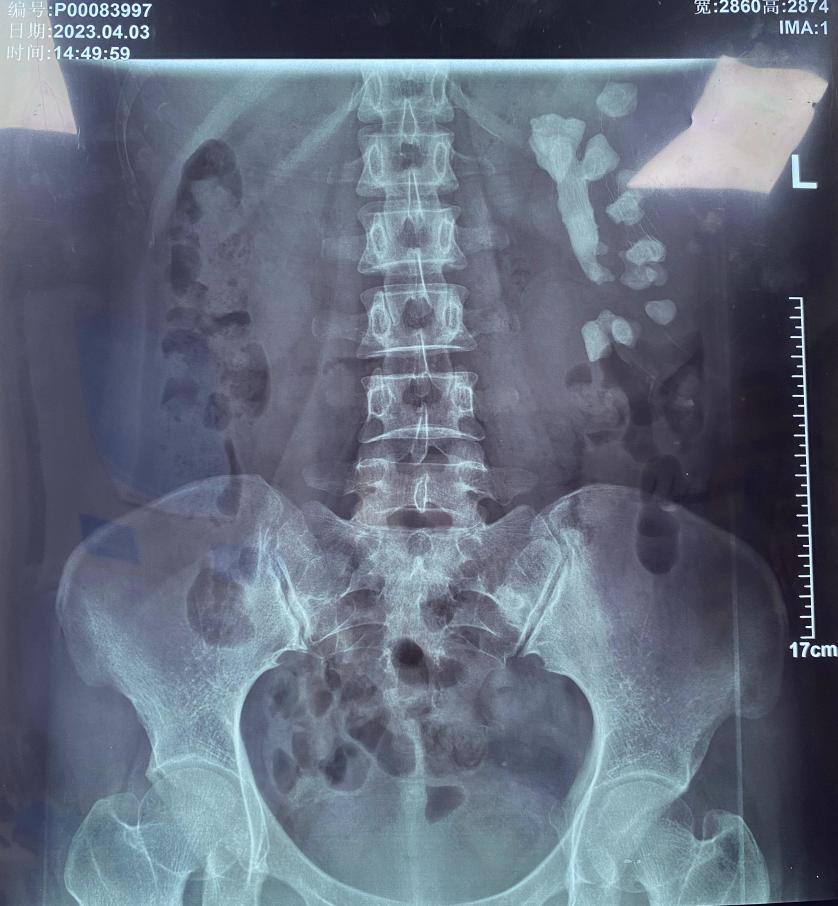

從不體檢,腎臟先天畸形不自知 超大號(hào)“珊瑚”結(jié)石險(xiǎn)撐壞女子左腎通訊員 金京“我也不知道結(jié)石是什么時(shí)候長(zhǎng)的,從來都不痛?!弊罱?,來自湖南的宋女士是一肚子苦水,左腎···